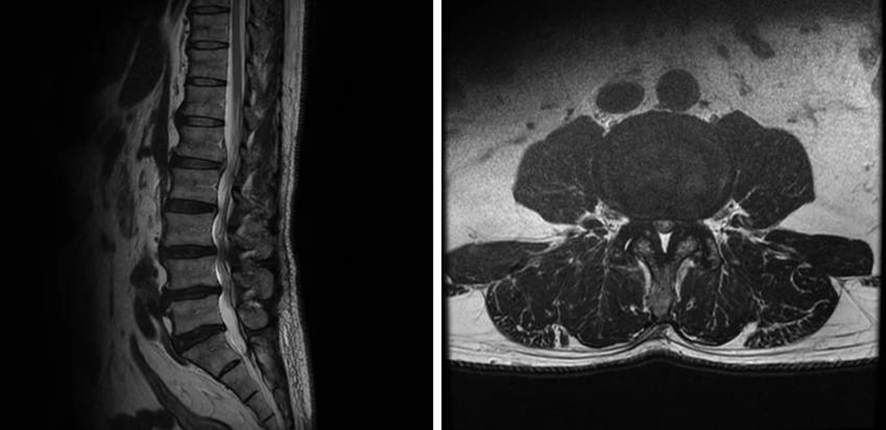

背骨の中にある神経の通り道(=脊柱管)が狭くなった状態は、脊柱管狭窄症といいます。

脊柱管狭窄症とは、神経の通り道である脊柱管が狭窄する(=狭くなる)ことにより、神経が圧迫される状態です。腰椎が不安定なことが原因の場合、身体の動きで痛くなることが多いです。